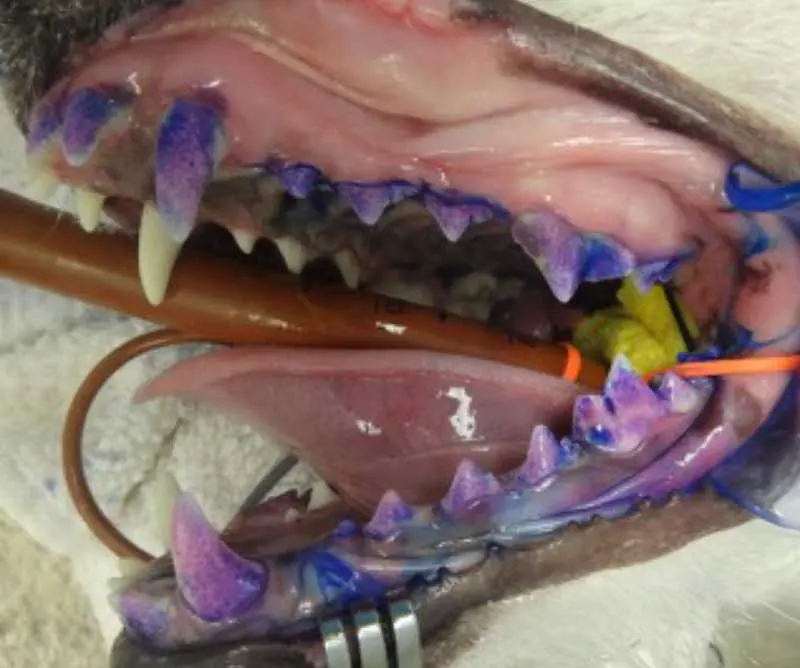

Gingivitis is the mildest form of periodontal disease (Figure 2). At this stage, the gingiva becomes inflamed. Plaque forms at the gingival margin, but the attachments and surrounding bone are unaffected.

Remember that plaque is not always visible to the naked eye, so applying a plaque-disclosing solution can help highlight any areas which may be of concern (Figure 3). Gingivitis is usually reversible with appropriate home care, and symptoms may include:

Stage 2 – early periodontitis

At stage 2, the inflammation extends below the gum line, affecting the supporting structures of the teeth (Figure 4). Osteolysis can be radiographically noticeable, with up to 25% bone loss.

Stage 3 – moderate periodontitis

The attachment loss continues to progress, with 25% to 50% bone loss. Periodontal pockets form between the teeth and gingiva, and furcation of the teeth becomes exposed, harbouring bacteria and leading to further damage (Figure 5).

Stage 4 – advanced periodontitis

In the advanced stage of periodontal disease, bone loss exceeds 50%. At this point, tooth loss is common due to the loss of the alveolar bone and periodontal ligament. The patient may experience significant pain and discomfort (Figure 6).